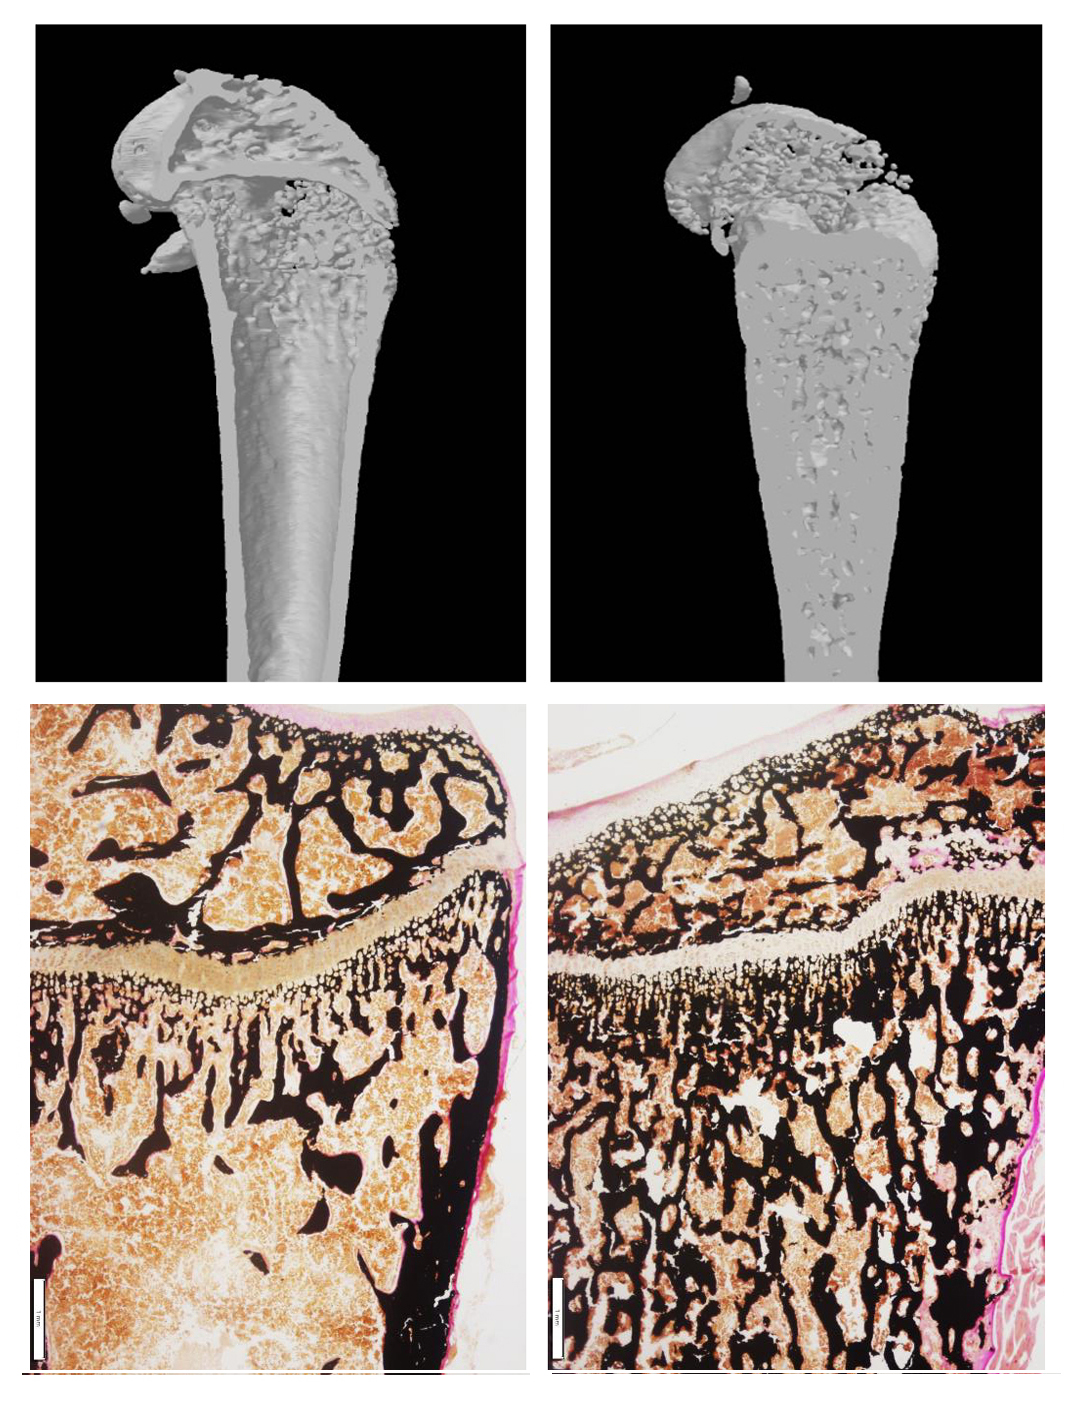

Und auch den molekularen Ursachen der Marmorknochenkrankheit sind die Forschenden auf der Spur: Ausgehend von der neu entdeckten Mutation haben die israelischen Kooperationspartner um Professor Ari Elson die Osteopetrose in Mausmodellen simuliert. So können die Forschenden die Auswirkung der Erbgutveränderung bis auf die molekulare Ebene ergründen. „Als Ursache der Osteopetrose hatten wir mit einer fehlerhaften Bildung der knochenabbauenden Zellen, der so genannten Osteoklasten, gerechnet. Doch im Modell haben wir einen ganz anderen Mechanismus entdeckt: Tatsächlich vereinigen sich Vorläuferzellen aus dem blutbildenden System zu gigantischen Osteoklasten. Eine ,Bremse‘, die den Fusionsprozess stoppt, greift hier nicht“, erklärt Professor Jan Tuckermann. Die Bildung dieser Riesenzellen könnte also Krankheitsursache und therapeutischer Ansatzpunkt sein. Wie beim menschlichen Patienten bessern sich die Symptome der Osteopetrose im Mausmodell nach einer Knochenmarktransplantation: Die Größe der „Riesenzellen“ normalisiert sich und auch die Anzahl knochenaufbauender Zellen (Osteoblasten) steigt wieder an. Im Modell hatten die Forschenden nämlich weiterhin eine Abnahme der Osteoblasten beobachtet – womöglich durch eine fehlerhafte Informationsübertragung zwischen knochenabbauenden und knochenaufbauenden Zellen.